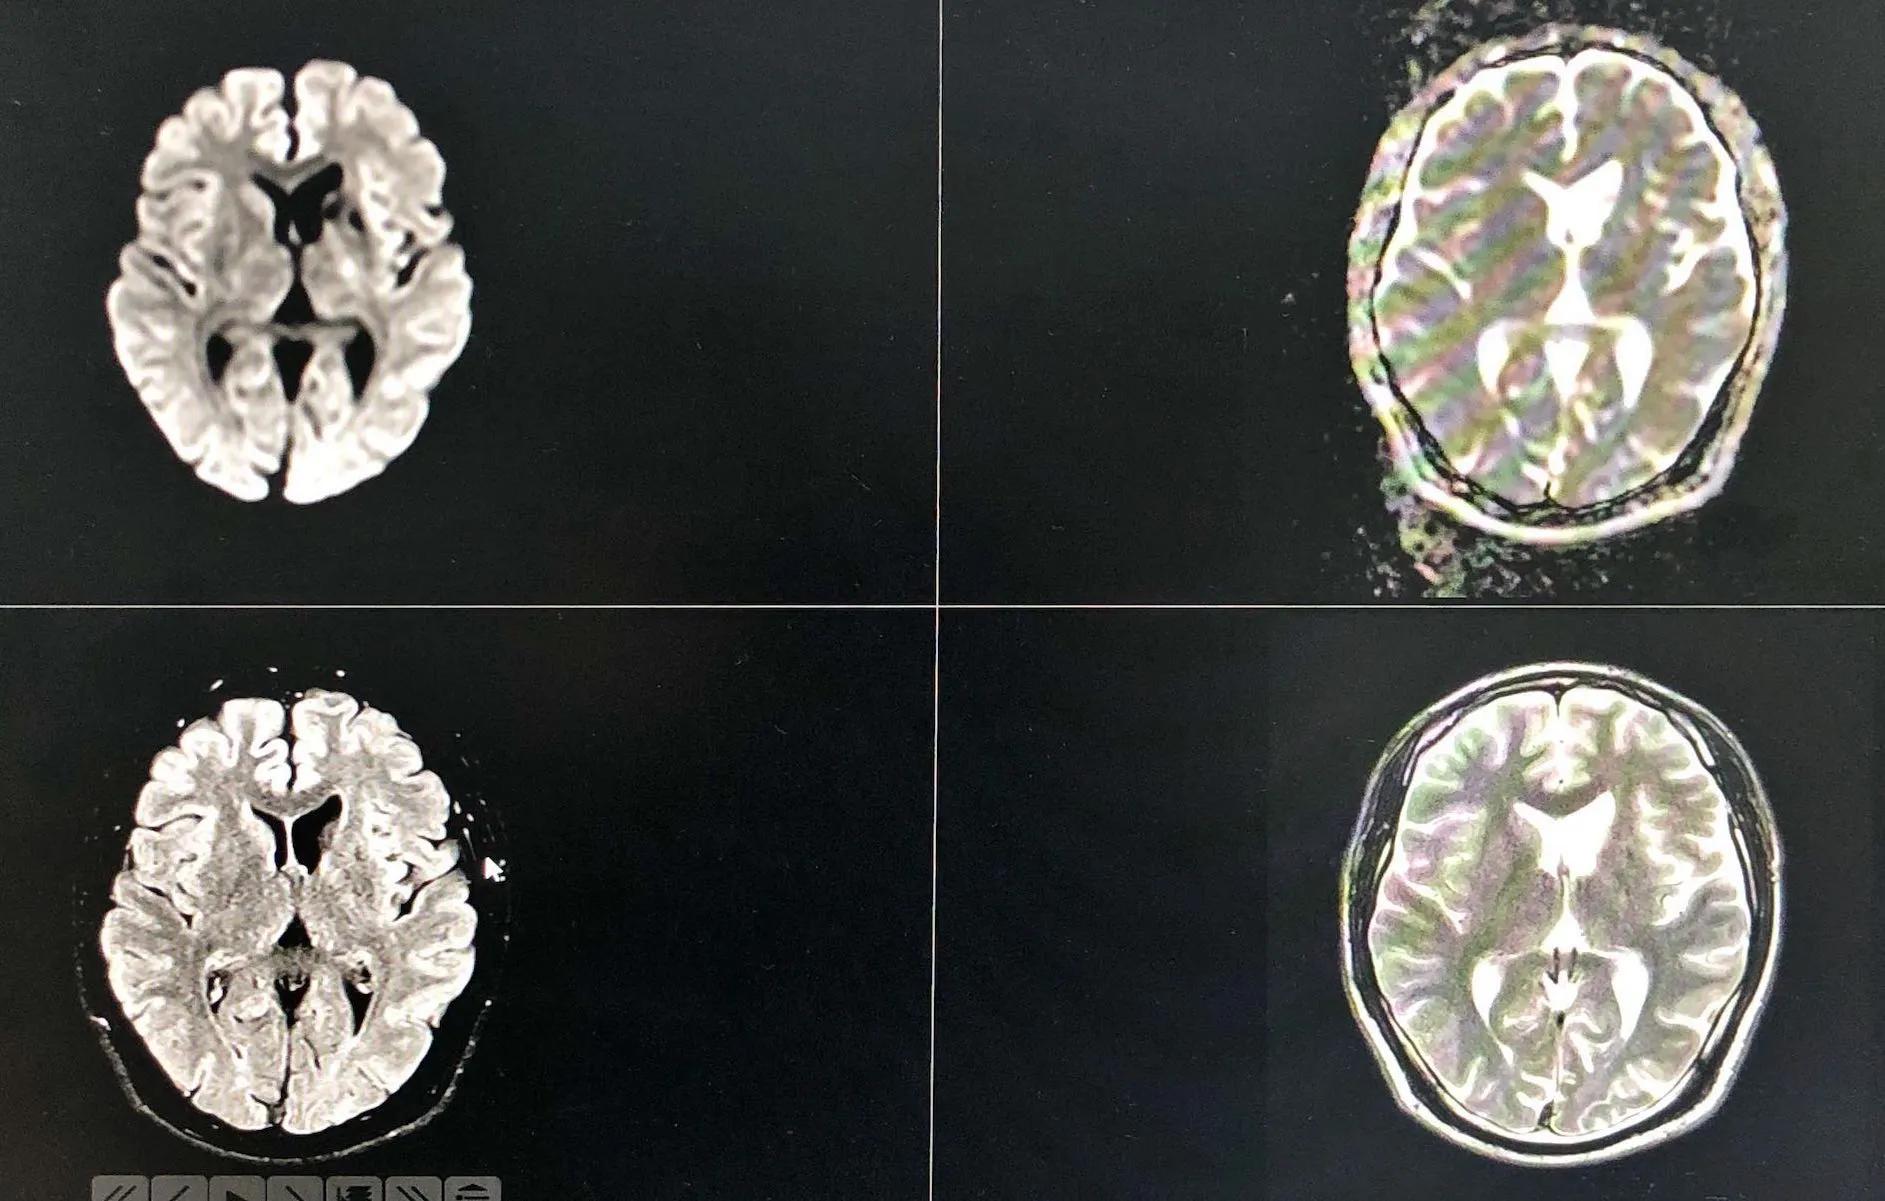

病例3:男,19岁,以“发作性右侧面部、右侧肢体麻木2天,再发加重4小时”为主诉入院。2天前熬夜后(已连续熬夜2周后休息1天)突然出现右侧面部、右侧肢体麻木,无头痛头晕、呕吐、言语不清,无视物重影、饮水呛咳、吞咽困难,无肢体无力及意识障碍等,持续约15分钟后完全缓解,未在意。4小时前患者再次出现右侧面部、右侧肢体麻木,伴言语不清、右侧肢体无力,右上肢可上抬,右下肢行走需搀扶,症状持续约30分钟完全缓解,后上述症状又反复发作3次,为求进一步治疗,急来我院,急查头CT:未见出血,急查头磁共振提示“颅内多发脑梗死”,急诊以“脑梗死”收入我科。3.既往史:吸烟史6年余,平均6根/天;否认“冠心病、高血压病、糖尿病”史;神经系统:神清,语利,智能可,双侧鼻唇沟对称,伸舌居中,四肢肌张力正常,肌力Ⅴ级,四肢腱反射(++)。双侧痛觉对称存在,双侧指鼻试验、跟膝胫试验稳准,双侧巴氏征(-),脑膜刺激征阴性,NIHSS评分:0分;磁共振(2017.07.01我院):1.左侧额顶叶、基底节区、侧脑室旁异常信号,考虑:急性期脑梗塞(TSI:貌似TIA的脑梗塞);颅脑MRA左侧大脑中动脉M1段纤细、远端血流显影浅淡……

图片来源于病历

入院后完善相关检查:颅脑CTA:1.左侧大脑中动脉M1段局部中度狭窄;2.左侧后交通动脉开放;高分辨磁共振成像示左侧大脑中动脉M2段重度狭窄伴动脉粥样硬化斑块形成(考虑不稳定斑块)